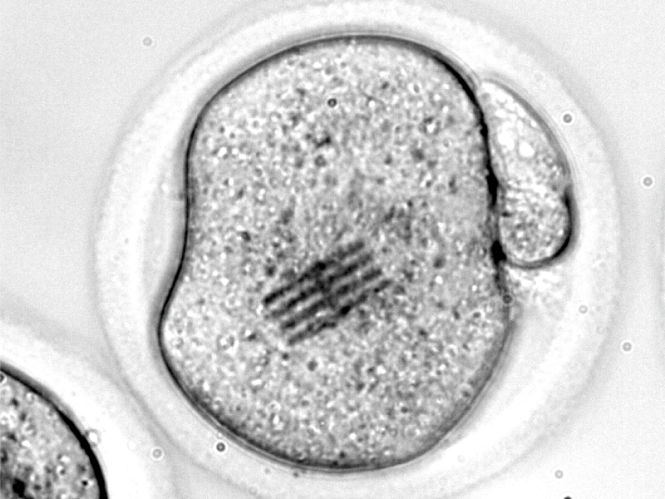

Los científicos han inyectado el chip en el interior de un óvulo de ratón junto con un espermatozoide para estudiar las etapas iniciales de la fertilización. El dispositivo, que funciona como sensor mecánico, es extremadamente minúsculo: mide apenas 22 por 10,5 micrómetros, tiene un grosor de 25 nanómetros (tres veces menor que el de un virus como el SARS-CoV-2) y una longitud 3 veces más pequeña que el diámetro de un cabello humano. Con el chip dentro, los científicos han podido medir las fuerzas que reorganizan el interior del óvulo, es decir, su citoplasma, desde que se introduce el espermatozoide hasta que se divide en dos células.

En cuanto a las mediciones, José Antonio Plaza, investigador del CSIC en el IMB-CNM que lidera este trabajo, señala que "nosotros vemos a través de microscopia óptica cómo el chip se dobla en el interior de la célula".

"Dado que conocemos perfectamente qué fuerza hay que aplicar para que se doble el dispositivo de una determinada manera, y lo hemos modelizado, visualizar la curvatura nos permite inferir qué fuerzas mecánicas se están dando en el interior de la célula", añade.

También se ha observado que el efecto de la membrana del embrión, que es más rígida que su interior, es la responsable de que los pronúcleos (núcleos que transportan el material genético de la hembra y del macho) converjan en el centro del embrión para fusionarse. Durante la fusión, no se han detectado fuerzas. Esto podría ser así, dicen los científicos, porque de esa forma se facilita la reorganización de los cromosomas.

La siguiente etapa es la división de la primera célula en dos. Aquí, los científicos han visto cambios en la rigidez del citoplasma. "En este momento, nuestros chips revelan que el citoplasma se hace más rígido, hecho que facilitaría la transmisión de las fuerzas dentro del embrión para conseguir elongarse", señalan los autores. Esta elongación es necesaria para la posterior división en dos células. Después, en el momento en que la célula se divide en dos, el citoplasma es menos rígido, posiblemente para facilitar la división.